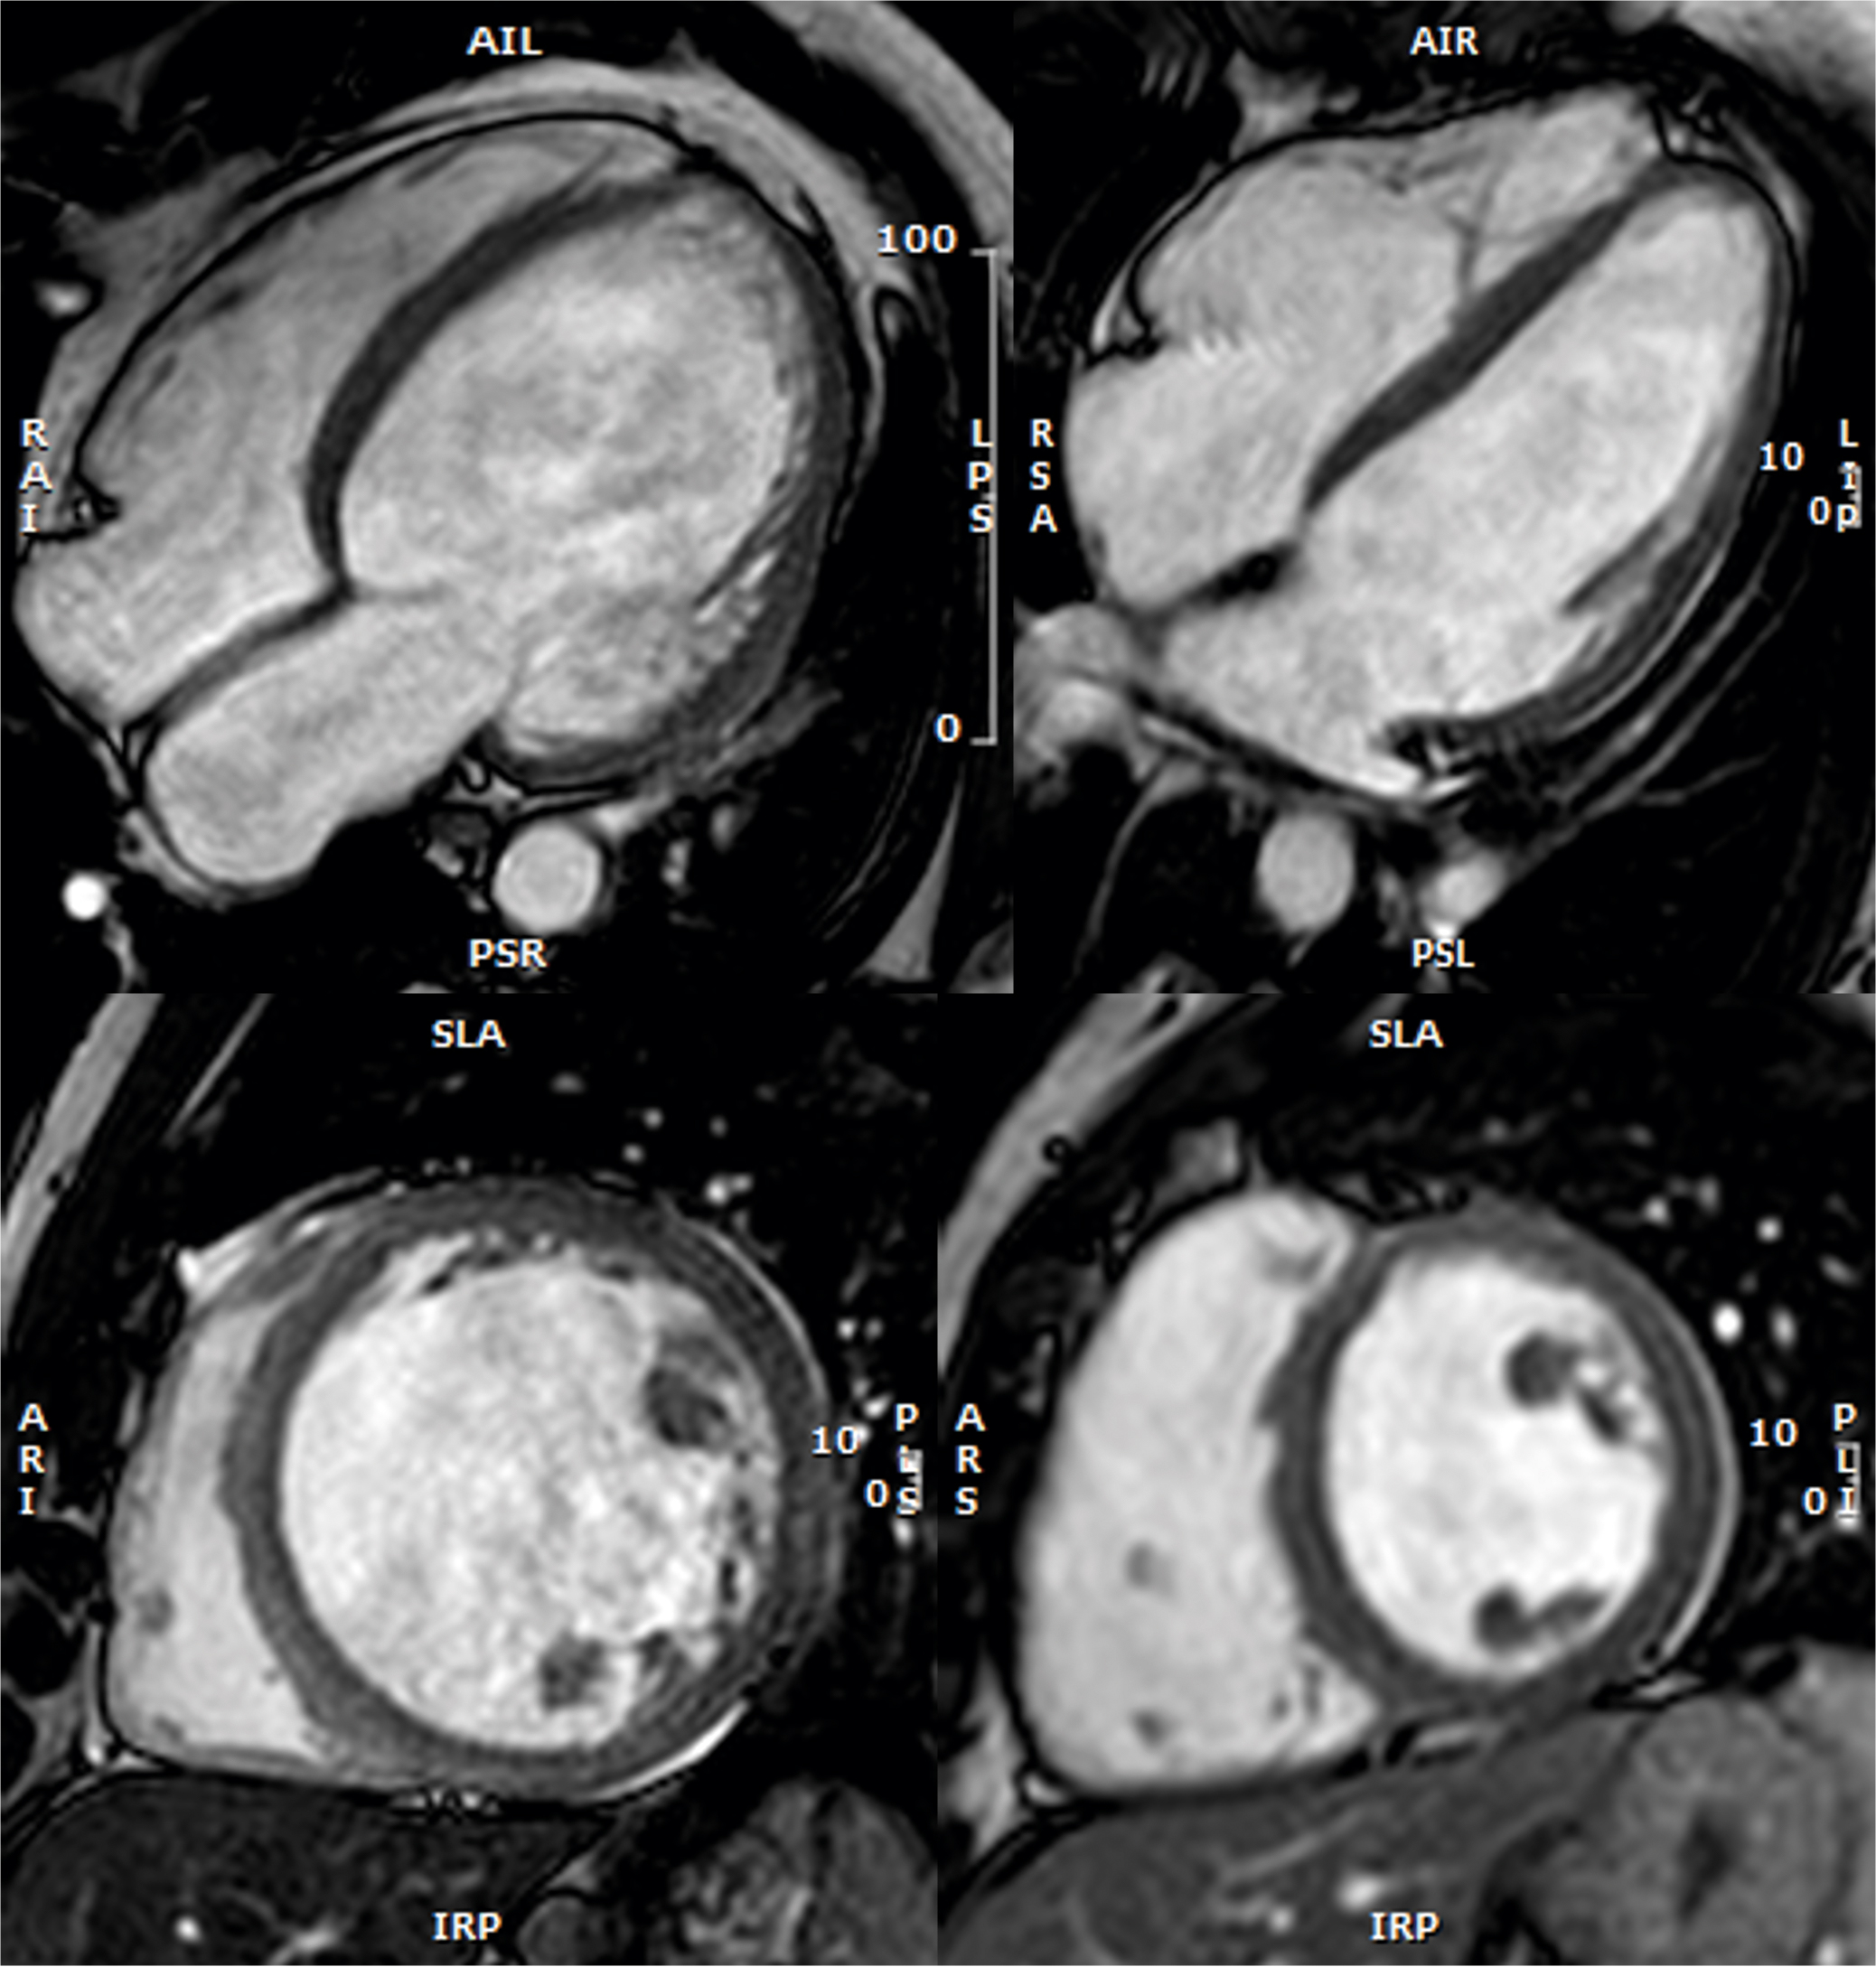

MRVALVE: MULTIMODALITY MYOCARDIAL TISSUE CHARACTERIZATION IN PATIENTS WITH SIGNIFICANT VALVULAR DISEASE

The MRVALVE study uses a multimodality imaging approach (cardiac magnetic resonance [CMR] and strain echocardiography) to better characterize left ventricular (LV) status in patients with significant valvular heart disease (VHD), focusing on aortic valve stenosis (AS) as a model of LV pressure overload and mitral regurgitation (MR) as a model of LV volume overload.

VHD significantly impacts LV dimensions, function, and tissue composition, all of which play a critical role in clinical decisionmaking. Current guidelines recommend surgical treatment for patients with significant VHD when symptoms develop or when there is evidence of LV remodeling or dysfunction. The most common forms of VHD are AS and MR. The progression from asymptomatic to symptomatic disease, or from normal LV function to LV dilatation, hypertrophy, and dysfunction, is driven by changes in tissue composition—primarily cardiomyocyte death, extracellular volume expansion, and fibrosis.

While surgery or percutaneous valve repair or replacement are effective treatments for severe VHD, interventions are typically based on the presence of symptoms or significant LV dysfunction. By the time these features appear, it is often too late to fully restore heart function. This highlights the need for tools for the early detection of myocardial involvement in asymptomatic VHD patients, allowing timely intervention before irreversible damage occurs.

Strain echocardiography, the best imaging modality for evaluating active LV myocardial deformation, can detect impaired multidirectional strain even when overall LV function appears normal. In the MRVALVE study, we correlate imaging data with functional assessments from the 6-minute walking test, which provides an objective measure of exercise capacity. Additionally, cardiac computed tomography is used to assess calcium deposition in the coronary arteries and heart valves, providing a calcium score that serves as both a diagnostic and prognostic tool in AS patients.

To date, 71 patients have been recruited, and all have completed their 1-year follow-up visit.